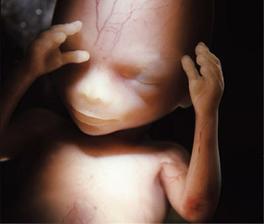

Jak asi víte, těhotenství je členěné na tři časové úseky, kterým říkáme trimestry – každý z nich trvá tři měsíce. Každý z trimestrů je zcela specifický, probíhají v něm určité charakteristické změny, podstupuje se vyšetření a nesou s sebou jiné pocity a obavy nastávající maminky.

S blížícím se koncem těhotenství se zvyšuje i netrpělivost. Objevuje se obava ze samotného porodu a z faktu příchodu nového člena rodiny.

Lékaři počítají týdny těhotenství od prvního dne poslední menstruace před otěhotněním. V prvních dvou týdnech tehotenství tedy žena těhotná není, protože k oplodnění vajíčka dochází až zhruba 14 až 21 dní od začátku menstruace.